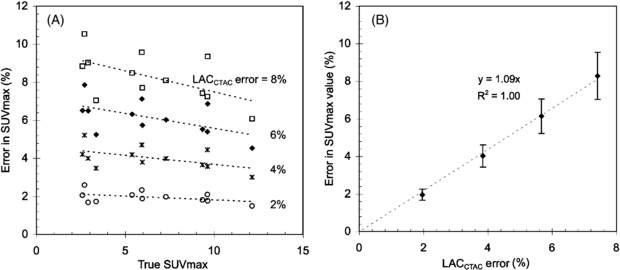

The estimated bias in SUVMAX as a function of 'true' SUVMAX is presented in figure 8(A) for each LACCTAC bias (−2%, −4%, −6% and −8%) introduced to the 12 lesions from five patient emission images. Here 'true' SUVMAX was found using the default LACCTAC because LACTX were not available for these images.

Figure 8. (A) SUV errors as a function of nominal SUV values for different values of percentage of CTAC error (LACCTAC error). (B) SUV errors as a function of percentage of error in CTAC (LACCTAC error (%)) averaged over all nominal SUV values.

Standard imageWhen the results are averaged for all SUV values (figure 8(B)) there is an approximate error in SUVMAX of 1% for each percentage error in LACCTAC, which is in agreement with our previously reported results for soft tissue (Kinahan et al 2006). The variability in the SUV bias also increased approximately linearly with the error in LACCTAC (figure 8(B)). There was a weak inverse dependence of bias in SUVMAX on the true SUV value (figure 8(A)). Similar results to those described above for SUVMAX were found for SUV75.

While the results from tables 3 and 4 determine the impact of errors in LACCTAC on PET SUVs, they do not take into account the important effects of the location and size of attenuating material in patient images. To include these effects and perform a more extended sensitivity analysis, we used five additional patient images with significant FDG uptake in bone lesions (e.g. figure 7). This allowed estimation of the error in FDG uptake as a function of the error in the CTAC and nominal SUV uptake as shown in figure 8(A). From figure 8(B) we see that the per cent error in PET SUVMAX is roughly proportional to the per cent error in LACCTAC. Very similar results were found for SUV75 (data not shown). These results are consistent with our previous results for soft tissues (Kinahan et al 2006). As expected, the variability of SUV measurements increased with increasing error in LAC factors because of the propagation of error from multiplicative terms.

Based on figure 8(B), with a typical error in LACCTAC of up to −3.1% at 140 kVp and up to −6.8% at 120 kVp, we would thus expect an SUVMAX error of approximately −3.1% and −6.8% at 140 and 120 kVp. This represents a range for PET/CT imaging parameters on clinical scanners using the tri-linear transform method described above (figure 1 and table 1).